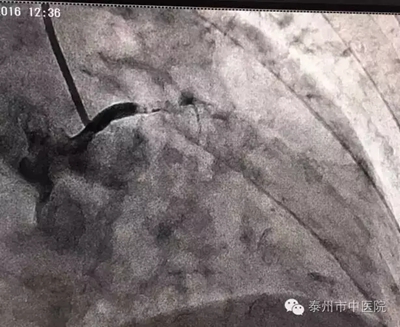

在與家屬溝通后,市中醫(yī)院心血管病科張永光主任等立即至導(dǎo)管室緊急冠脈造影。冠脈造影血管投影只見左主干近端,下方血管無顯影,明確為左主干閉塞。令現(xiàn)場所有醫(yī)護(hù)人員心驚不已!

左主干閉塞,是一例病情兇險(xiǎn)、病死率極高的病例!搶救刻不容緩!!張永光主任等,隨即開展緊急救援,長達(dá)一個(gè)小時(shí)的救治中,左主干再通,X線下可看見清晰的血管顯影。